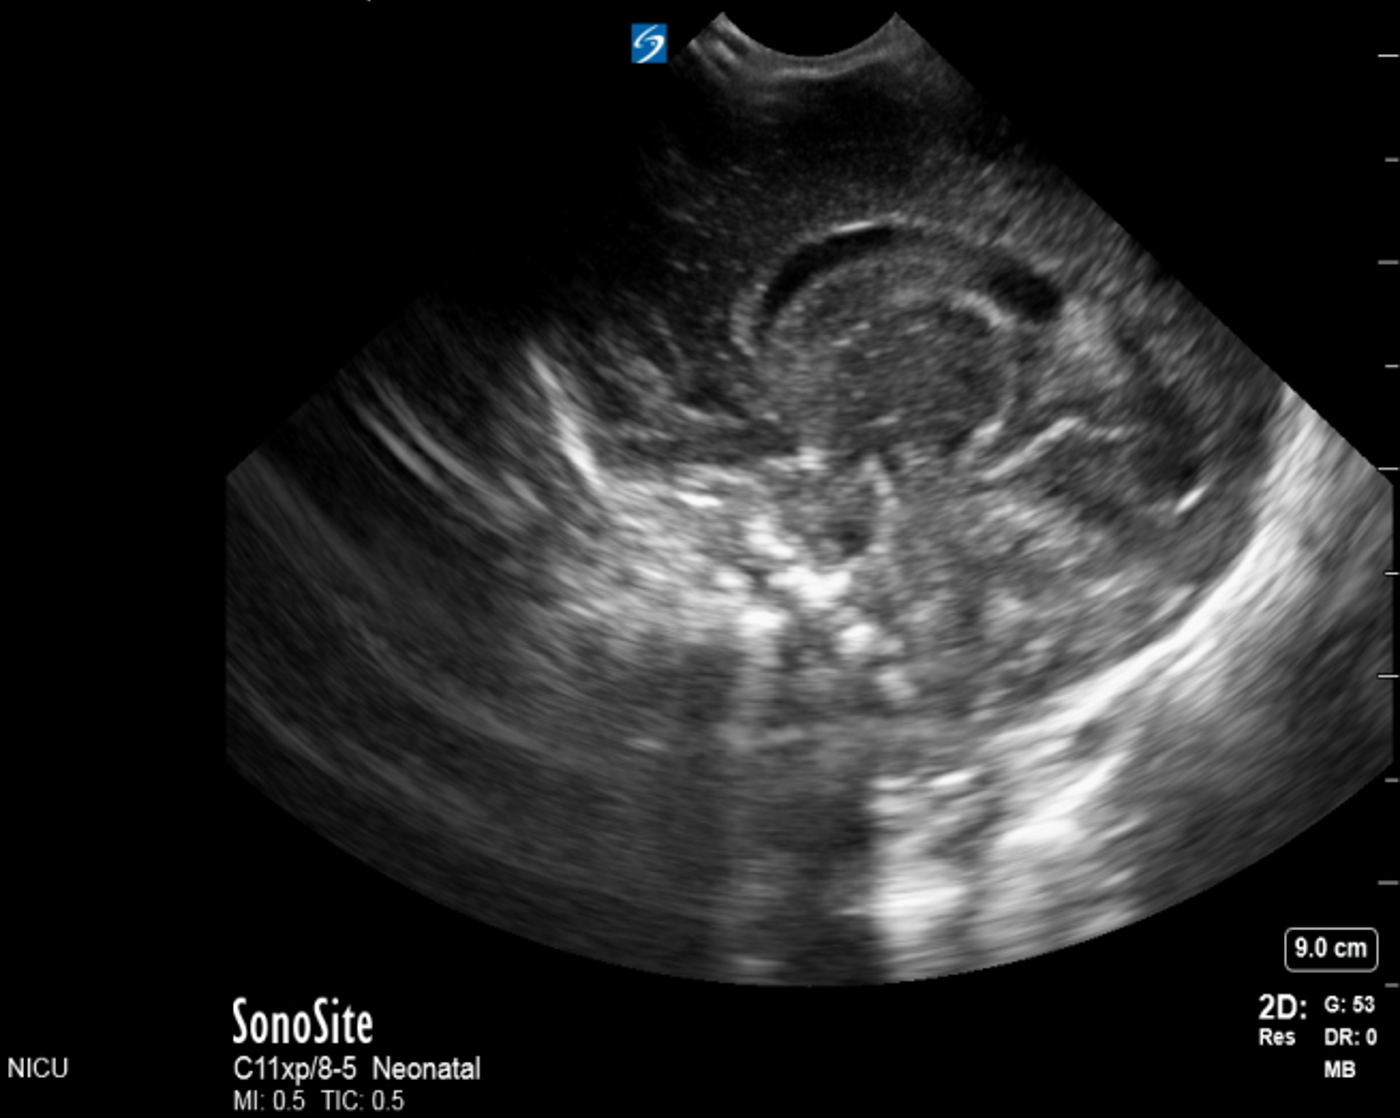

Neonatology Grade 2 IVH Sagittal 2 Image